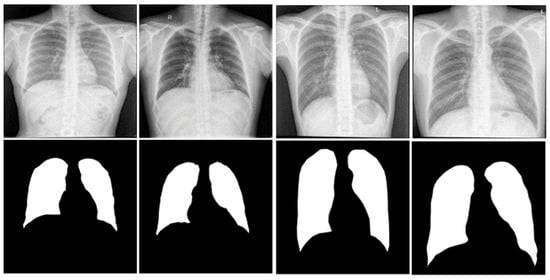

3.1.6. Segmentation of the Classification Dataset

3.1. Segmentation